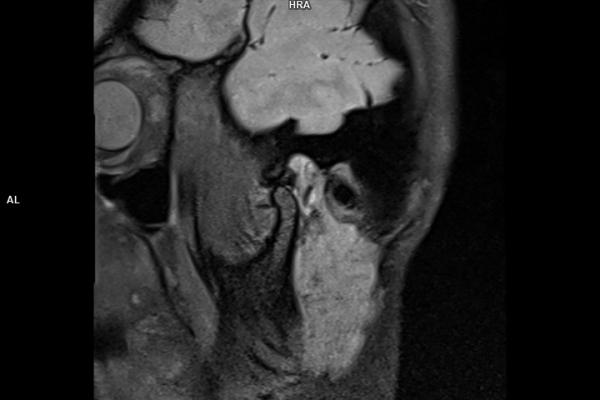

CT Untersuchung Bild

Detailbild MRT